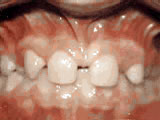

Spacing of Teeth

Gaps between teeth is a common issue we treat, and much like crowding is an imbalance in the size of the teeth and the space available for them to fit. Treatment options vary and braces or Invisalign can usually be used to correct this issue.